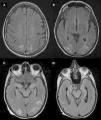

Al considerar el tipo de medicamento según la clasificación ATC, se incluyeron 9 fármacos antineoplásicos y 6 inmunomoduladores, de los cuales 5 fueron biológicos del grupo antiinfecciosos para uso sistémico. De estos fármacos, el 66,67% (n=10) fueron indicados para uso sistémico y el 33,33% (n=5) para uso neurológico. Con respecto a las RAM, el 73,33% (n=11) fueron a nivel del sistema nervioso y el 26,67% (n=4) fueron a nivel sistémico. Del total de RAM del sistema nervioso, el 73,73% (n=8) fueron en el sistema nervioso central (SNC) y el 27,27% (n=3) en el sistema nervioso periférico (SNP). Se reportaron 3 casos de síndrome de encefalopatía posterior reversible (PRES), 3 de encefalopatía, 3 de neuropatía, 4 de leucopenia (uno asociado a neutropenia), uno de cerebritis y uno de accidente cerebrovascular (ACV) isquémico. Con respecto a este último, se destaca que el mismo no estaba descripto en el prospecto del fármaco causal (venetoclax), por lo que se realizó una búsqueda bibliográfica hallándose un caso de ACV hemorrágico fatal reportado en el trabajo de investigación de fase II de desarrollo del mismo14 (fig. 1).

Accidente cerebrovascular isquémico secundario a venetoclax. (A-D) Lesiones isquémicas en territorio carotídeo izquierdo en secuencias DWI, FLAIR, T1 y GRE, respectivamente. (E) Angiorresonancia magnética intracraneal evidenciando ausencia de señal de flujo a nivel del origen de la arteria carótida interna izquierda.

Es de particular interés el caso del venetoclax, un fármaco recientemente aprobado como segunda línea para el tratamiento de la leucemia linfocítica aguda, cuyas RAM más frecuentemente reportadas son los trastornos del sistema sanguíneo, gastrointestinales e infecciones. En nuestro estudio, se describe un caso de ACV isquémico secundario al uso de este fármaco; una RAM no descripta en el prospecto del fármaco. Al realizar la búsqueda bibliográfica de esta RAM, si bien no pudimos encontrar casos de ACV isquémicos, encontramos un caso de ACV hemorrágico fatal reportado en el trabajo de fase II del desarrollo del fármaco14.